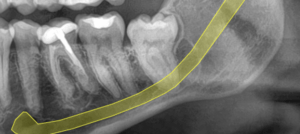

Radiografía inicial de tercer molar en íntima relación con el nervio alveolar inferior